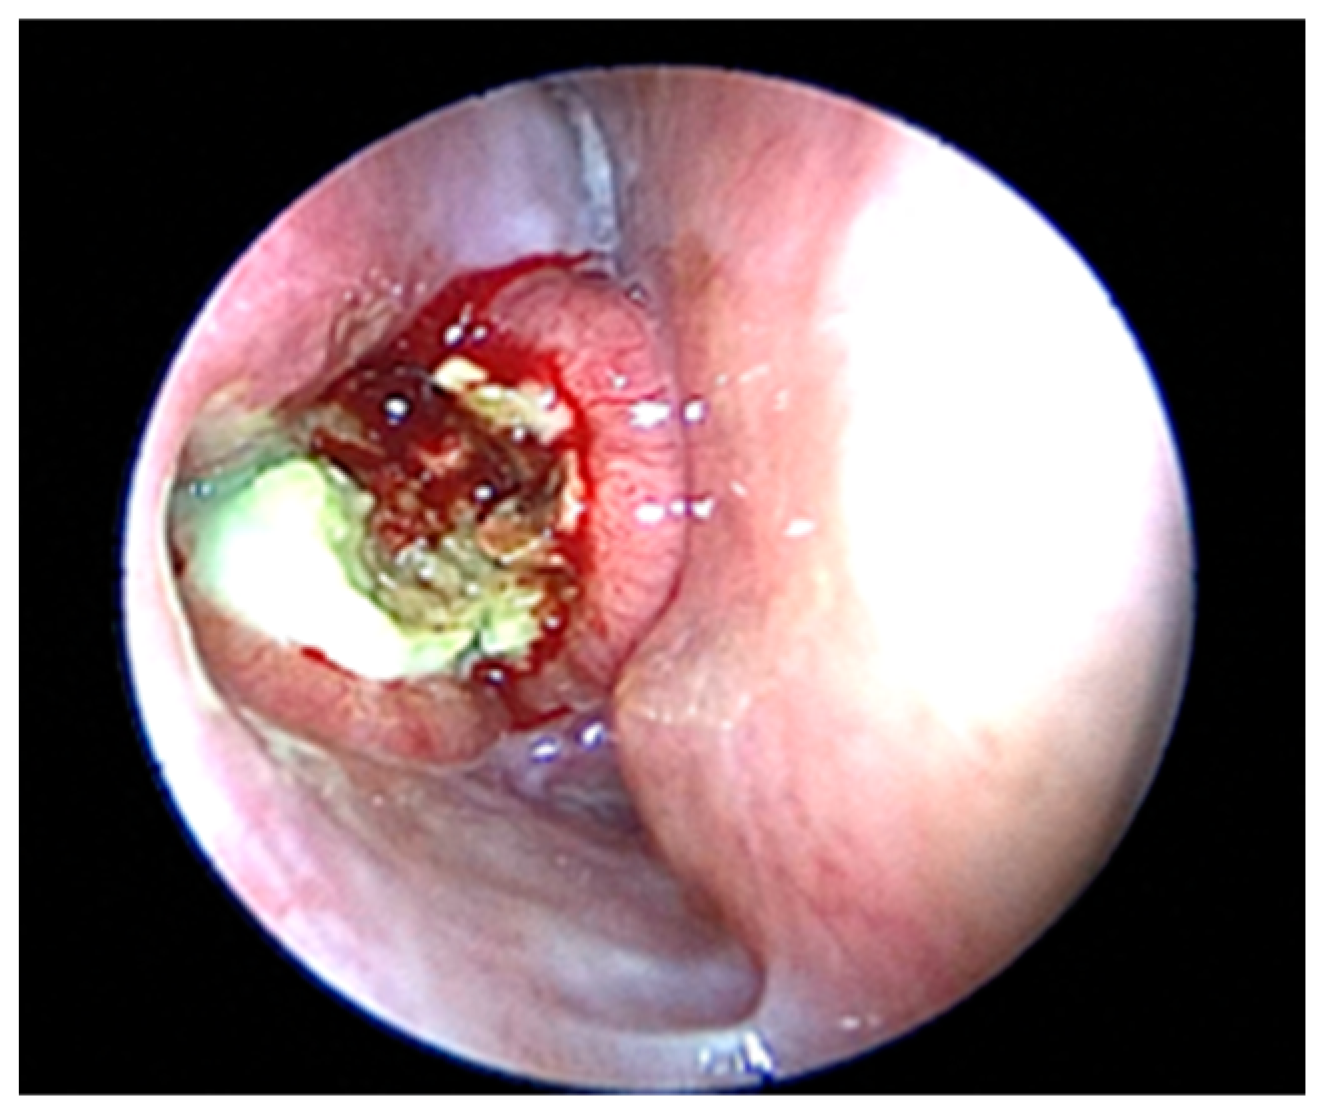

2. Case Presentation